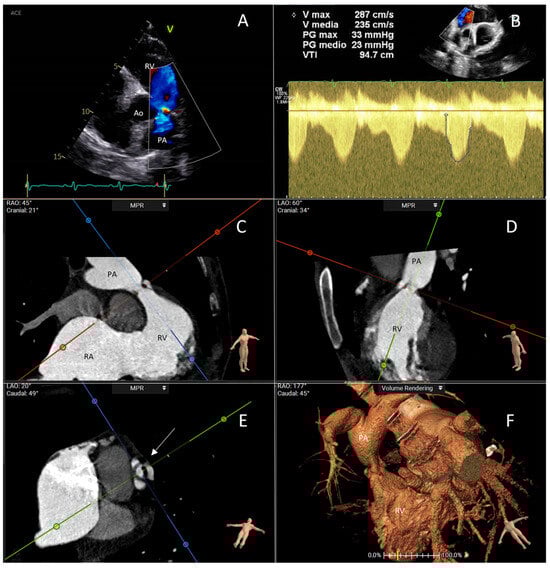

- Cammalleri, V.; Piscione, M.; De Luca, V.M.; Antonelli, G.; Cocco, N.; Nusca, A.; Gaudio, D.; Nobile, E.; Coletti, F.; Bianchi, A.; et al. Carcinoid Pulmonary Valve Stenosis: Multimodality Imaging and Transcatheter Valve Implant with Prestenting Technique. Circ. Cardiovasc. Imaging 2024, 18, e016785. [Google Scholar] [CrossRef] [PubMed]